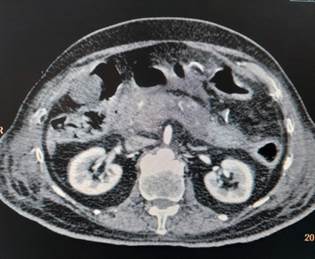

Her laboratory investigations revealed the following serum amylase 899 U/L, lipase 710 U/L, total leucocyte count 11500, Hb 14.1 g/dl, platelet count 1,90,000, serum aspartate aminotransferase 66 U/l, alanine aminotransferase 46 U/L, alkaline phosphatase 99 U/L, bilirubin total 0.9 mg/dl, blood urea nitrogen 27mg/dl, creatinine 0.5mg/dl, Na + 140 meq/l, K+ 3.5 meq/l, Ca 2+ 9.5mg/dl, phosphorus 3.5mg/dl. CT scan

Figure 1: Axial Contrast-Enhanced CT Image Showing Bilateral Kidneys and Abdominal Viscera

of abdomen (Figure 1) showed bulky/ enlarged and heterogenous pancreas with non-enhancing necrotic areas within it. Tail is poorly visualized (likely necrotic). Peripancreatic fat stranding with peripancreatic fluid is noted – features suggestive of acute necrotizing pancreatitis. As a routine protocol for admission in intensive care unit during this covid era, her nasopharyngeal and oropharyngeal swab was sent for COVID-19 testing by reverse transcriptase polymerase chain reaction (RT-PCR) which came out to be positive. Diagnosis of acute viral pancreatitis, COVID-19 induced, was kept. She was admitted in COVID-19 isolation ward and treated symptomatically with bowl rest, intravenous fluids, analgesia and empirical antibiotics. She was managed conservatively and discharged in hemodynamically stable condition after 1 week.